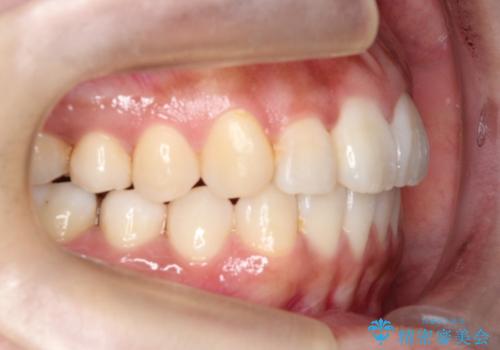

【引っ込んだ前歯が気になる、真ん中の線も揃えたい】インビザライン症例

- 前歯の歯並びの改善を希望され来院された患者様です。

初診時の歯並びの状態としては、上下ともに全体に及ぶの中等度のがたつき(叢生)があり、全特に左上の前歯は1本だけ引っ込んでいる状態でした。

抜歯は行わず上顎の奥のスペースを利用して歯をスライドする方法の他に歯列弓の拡大やディスキング(歯と歯の間の隙間を作る処置)を行い叢生を改善しました。

歯の大きさの不揃いが原因の正中のズレは、ディスキング量を調整することで合わせました。

見た目、嚙み合わせ及び、治療期間や施術内容に大変ご満足いただきました。